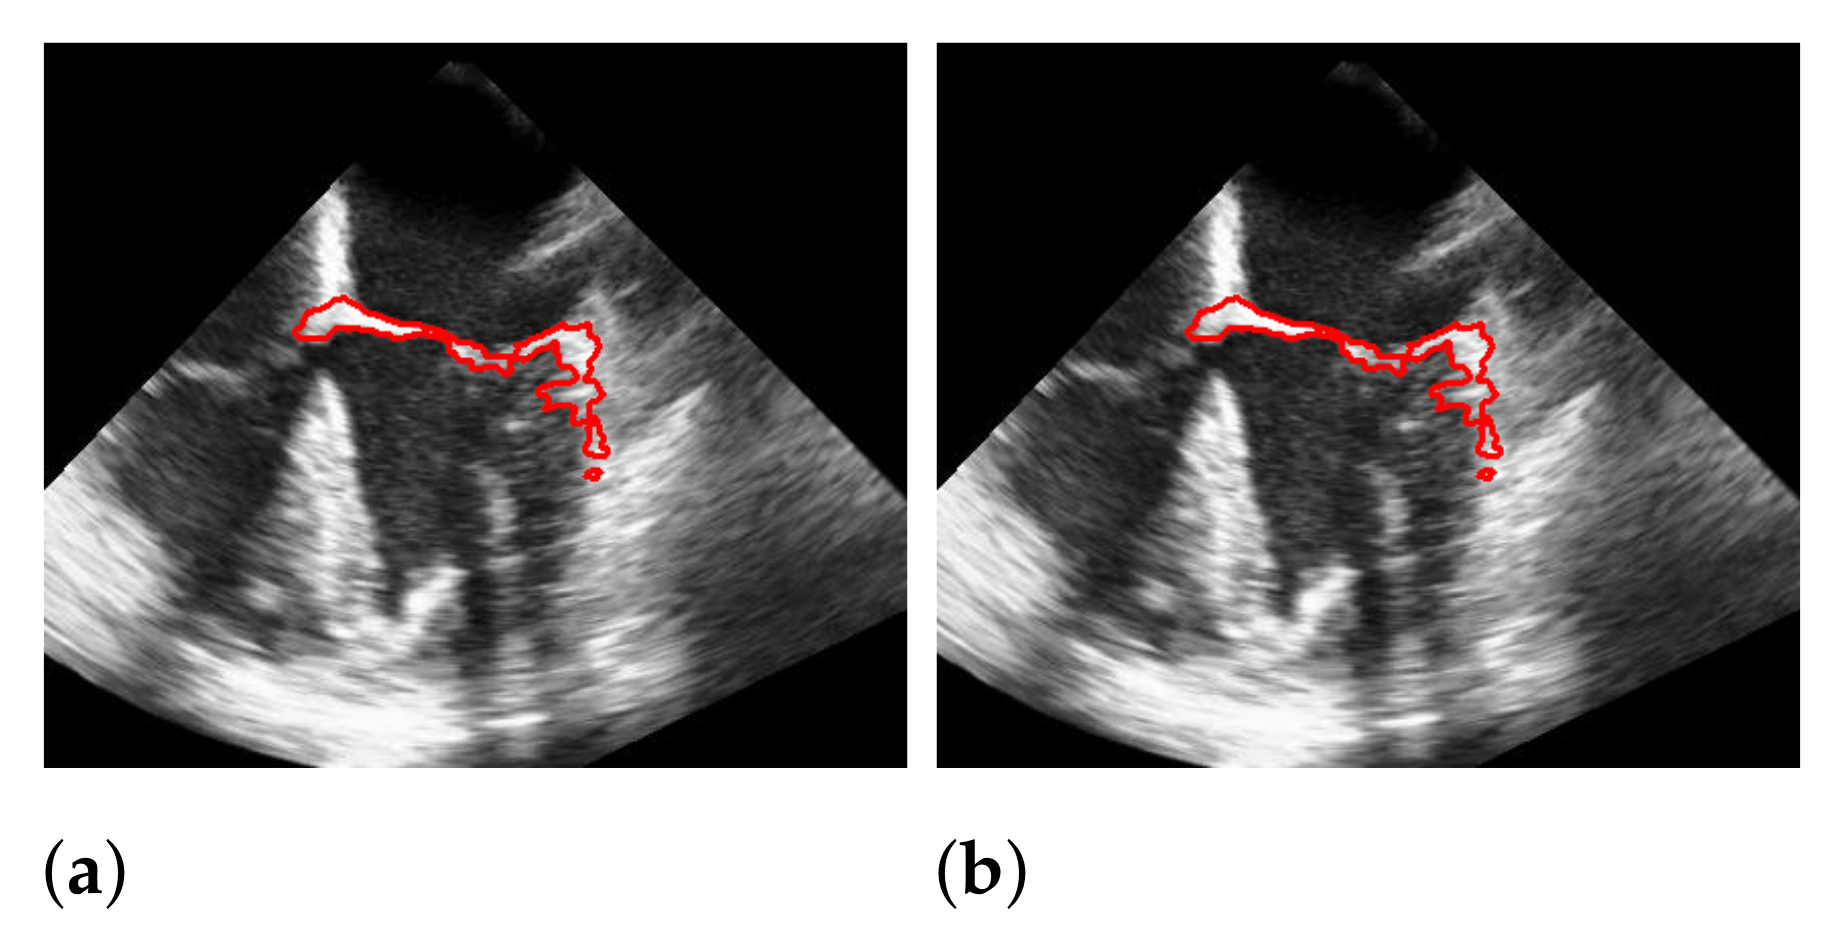

Figure 14.

Effect of applying windowing on segmentation. The red marks indicate the segmentation. (a) without windowing; (b) with windowing.